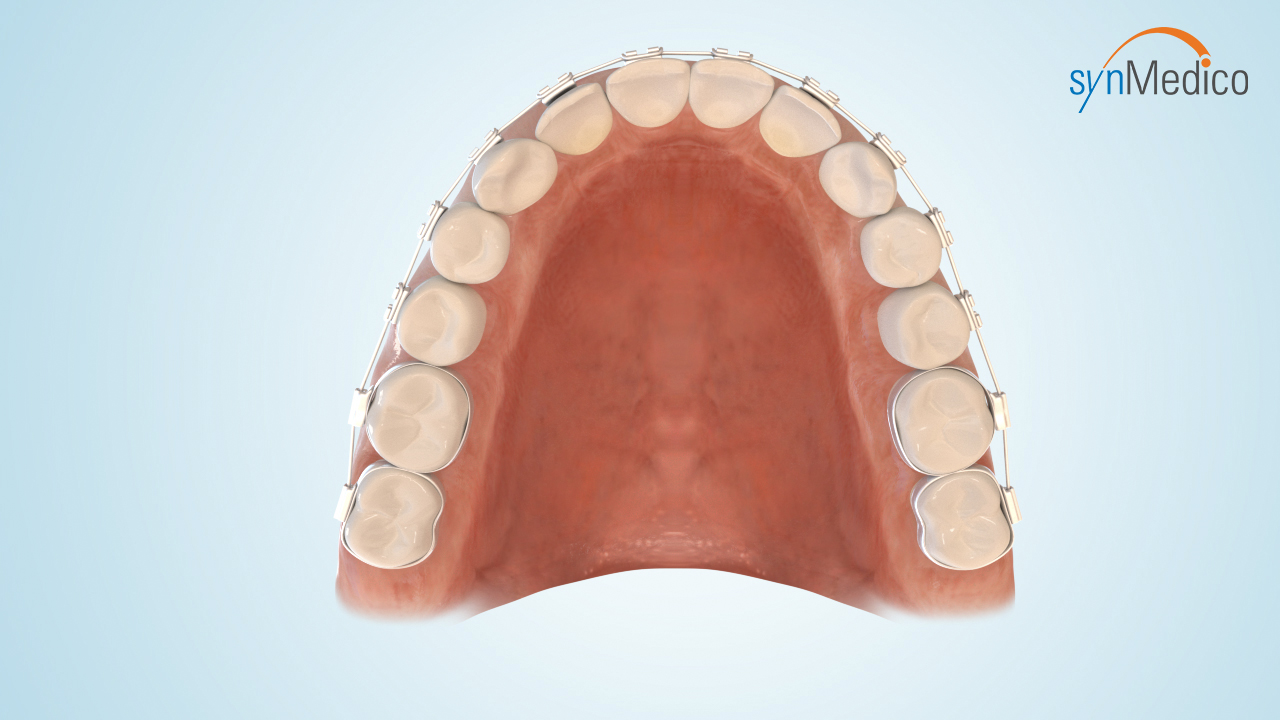

Freilegung von Zähnen

Gelegentlich verbleiben Zähne in der Wachstumsphase im Kiefer, da eine Blockade durch Nachbarzähne den Durchtritt verhindert. Durch eine kombinierte Behandlung mit den Techniken der Kieferorthopäde und der Kieferchirurgie können solche Zähne in die Zahnreihe eingestellt werden.